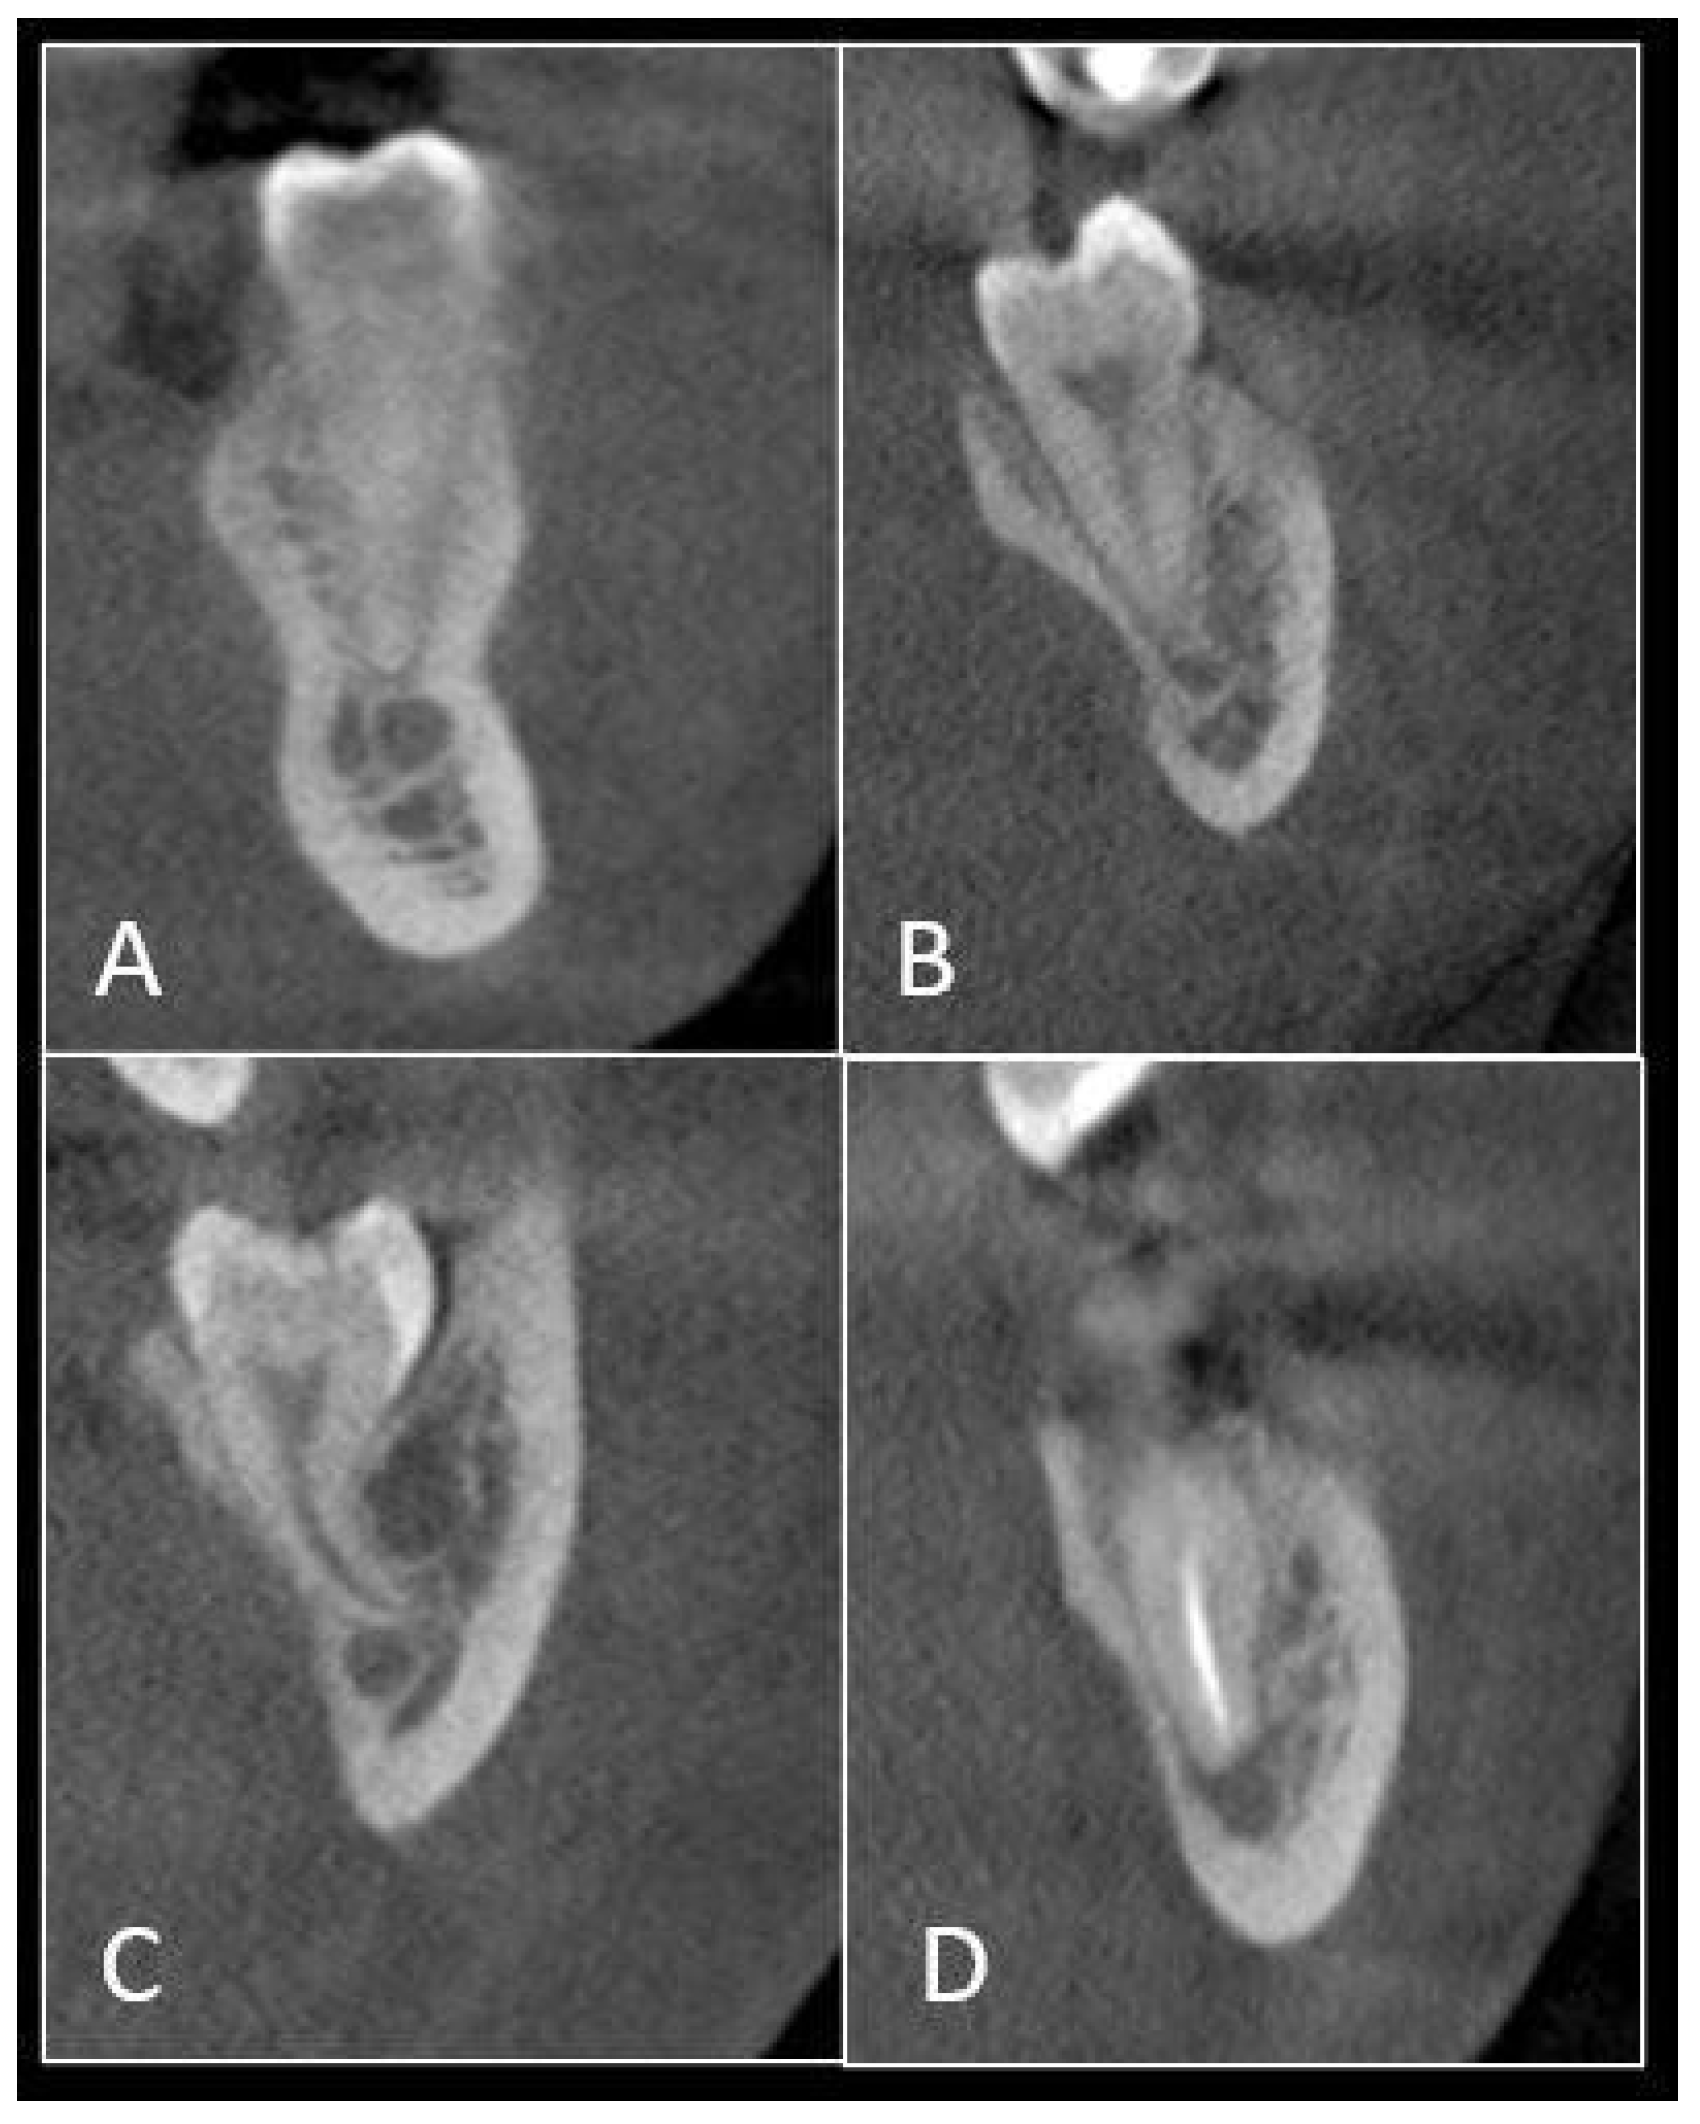

2.2. Imaging Analysis